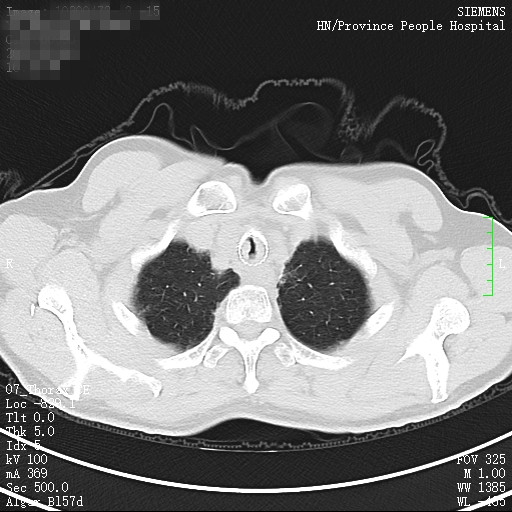

59岁的黄先生是一名气管鳞癌患者,3年前曾在我院呼吸二病区接受了紧急支气管镜手术,做了气管内肿瘤切除并置入金属支架,此次黄先生再次出现呼吸窘迫症状,当地医院立即联系将其转入呼吸二病区准备再次介入治疗。

完善术前检查后即将安排手术时,黄先生的健康码突然变为黄码,但其气管最窄段不足5mm,极度呼吸窘迫,手术不做,则生命危在旦夕,做,有暴露于病毒的可能。为此,呼吸二病区张卫东主任立即组织专家讨论,疫情面前,医务人员必须站在第一线,生命至上,创造一切条件积极介入治疗,挽救患者的生命。